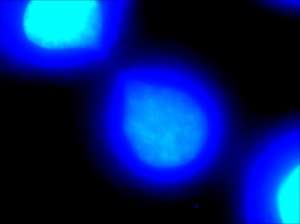

| DAPI staining allows for visualization of deoxyribonucleic acid portions of the two daughter cells. The thin “string-like” DNA connecting them is defined as a chromatin bridge. | |

Chromatin bridge is a mitotic occurrence that forms when telomeres of sister chromatids fuse together and fail to completely segregate into their respective daughter cells. Because this event is most prevalent during anaphase, the term anaphase bridge is often used as a substitute. After the formation of individual daughter cells, the DNA bridge connecting homologous chromosomes remains fixed. As the daughter cells exit mitosis and re-enter interphase, the chromatin bridge becomes known as an interphase bridge. These phenomenon are usually visualized using the laboratory techniques of staining and fluorescence microscopy.[1][2]

Chromatin bridges are easiest and most readily visible when observing chromosomes stained with DAPI. DNA bridges appear to be a blue, “string-like” connection between two separated daughter cells. This effect is created when sticky ends of chromosomes remain connected to one another, even after mitosis. A chromatin bridge may also be observed using indirect immunofluorescence, in which anti-tubulin emits a green coloration when bound to microtubules in the presence of UV light. Because microtubules maintain the positions of the chromosomes during mitosis, they appear to be densely pinched between the two dividing, daughter cells. Chromatin bridges can be difficult to locate utilizing fluorescence microscopy, as this phenomenon is not incredibly abundant and tend to appear faint against the dark background.